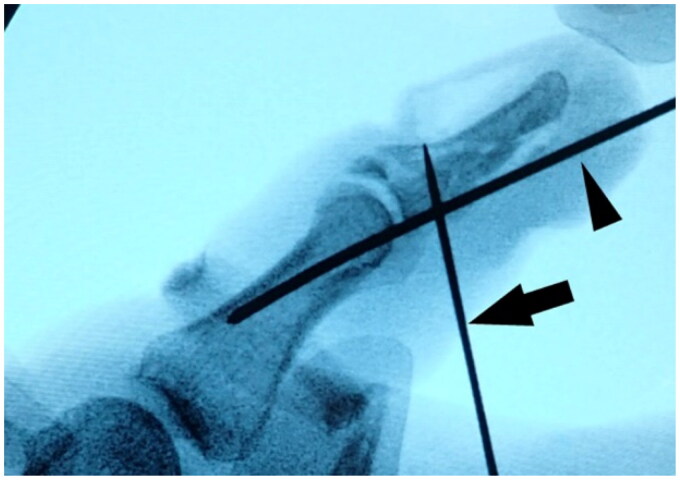

A distal phalanx may fracture in an atypical shape after high-energy trauma. A 61-year-old man sustained an open fracture of the distal phalanx of his left thumb while using a power saw. The fracture occurred in the coronal plane and the volar bone fragment was dislocated under traction by the flexor pollicis longus tendon. The patient underwent surgery the day after the injury. A flexion block pin was inserted to reduce the volar bone fragment, and an external flexion force was applied using a dorsal splint to compress the dorsal bone fragment into the volar bone fragment. The pin was removed 6 weeks postoperatively, and active range of motion exercises were started 8 weeks postoperatively. Bone union was achieved with good alignment, and although the interphalangeal joint remained slightly restricted in range of motion, the patient returned to his previous job and was satisfied with the function of the left thumb.

高能创伤后远端指骨可能以非典型形状骨折。一名61岁男子在使用电锯时左手拇指远端指骨开放性骨折。骨折发生在冠状面,掌侧骨碎片在拇长屈肌腱牵引下脱位。病人在受伤后的第二天接受了手术。插入屈曲块销以复位掌侧骨碎片,并使用背侧夹板施加外部屈曲力将背侧骨碎片压缩到掌侧骨碎片中。术后6周取下固定针,术后8周开始活动范围训练。骨愈合,对准良好,虽然指间关节的活动范围仍有轻微限制,但患者恢复了原来的工作,并对左手拇指的功能感到满意。